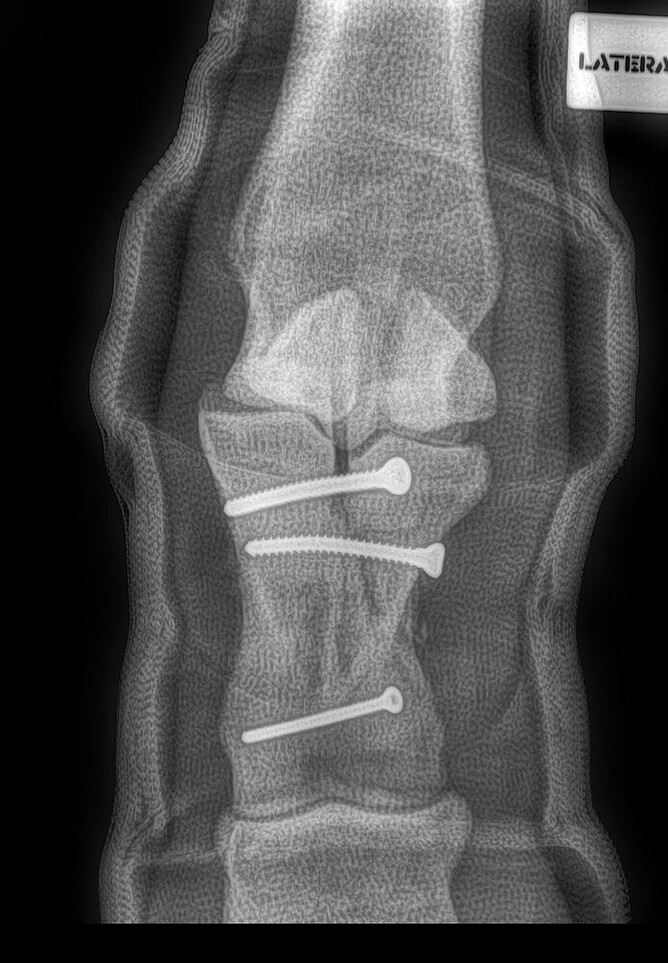

Figure 1 shows what can happen to a repair on anaesthetic recovery. If they struggle and flail, the repaired leg can be pulled apart or get damaged. In an effort to minimise the issues with anaesthetic recovery; many leg fractures are performed standing using sedation and local anaesthesia to numb the area. While this is technically more difficult, horses do not have to recover from anaesthesia.